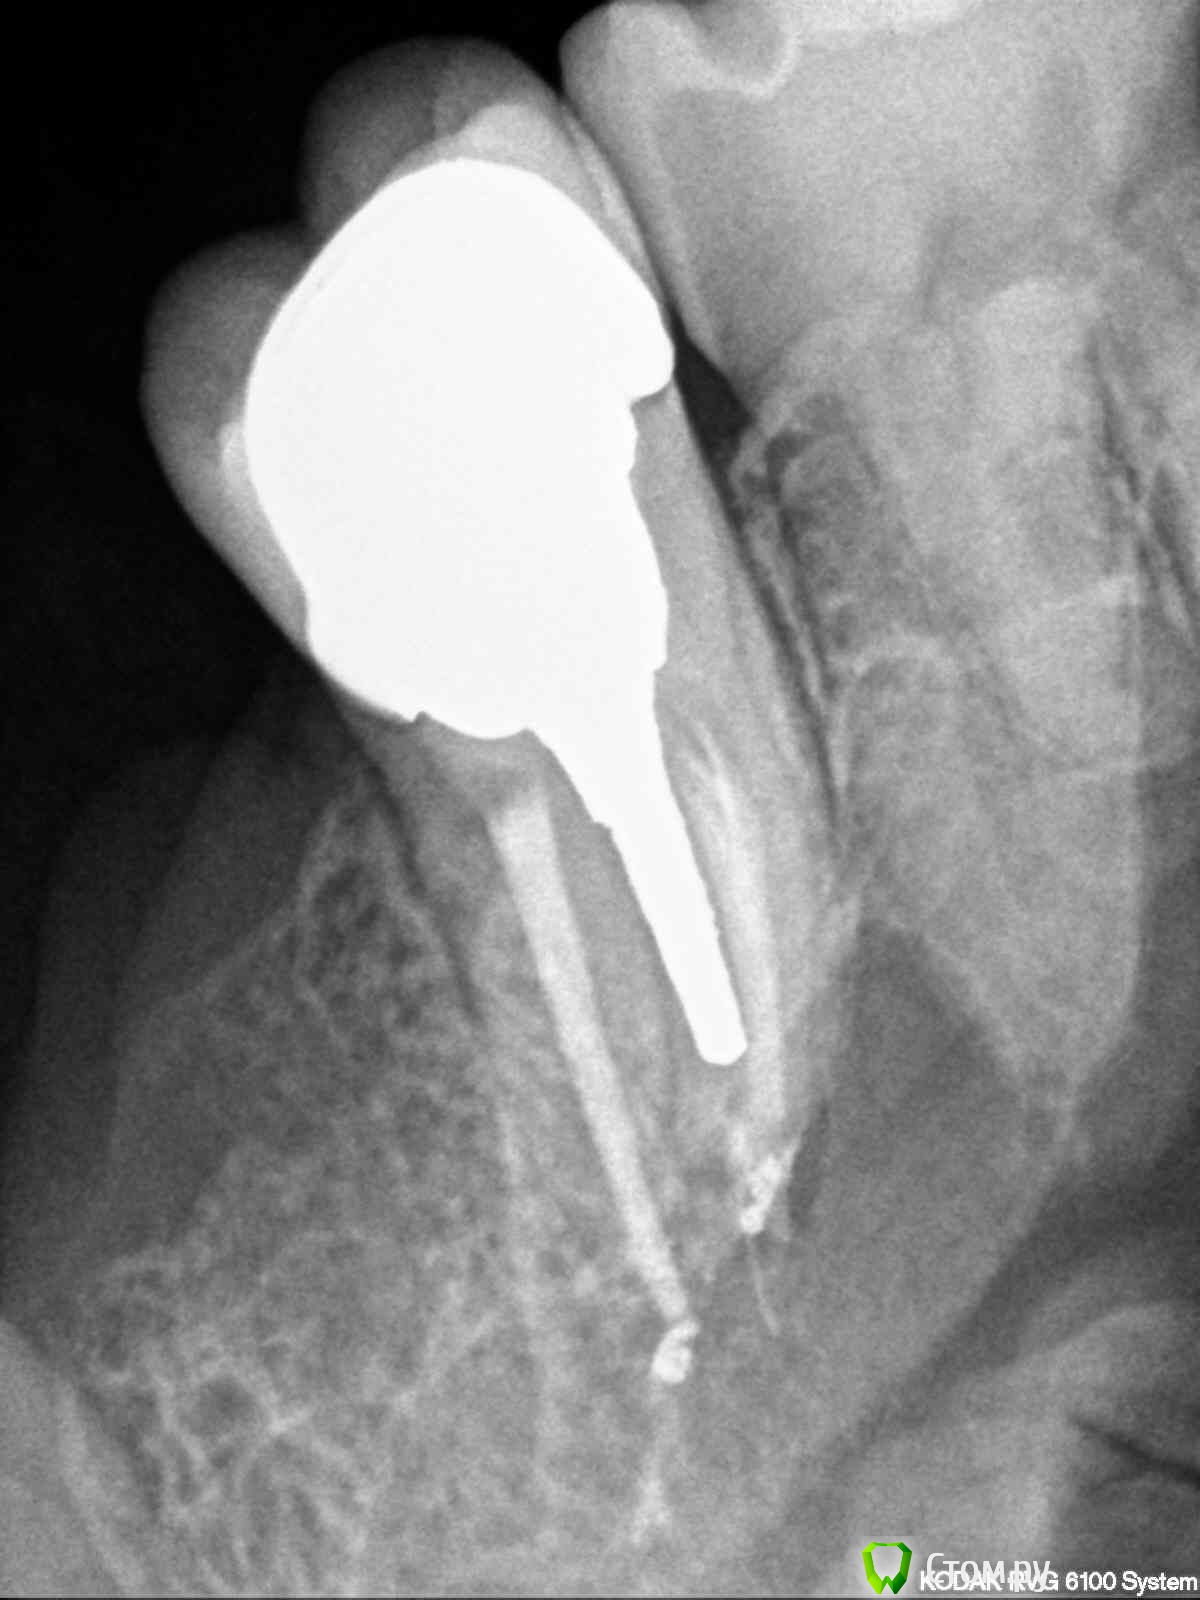

englishlady Опубликовано 6 ноября, 2013 Поделиться Опубликовано 6 ноября, 2013 Уважаемые врачи, оцените пожалуйста импланты. Меня стала беспокоить коронка на импланте 36. Хотелось бы понять, что не так до того как я пойду к врачу. Корнки на имплантах стоят на временном цементе. Десны не кровоточат. Заранее спасибо за ответ. Ссылка на комментарий

englishlady Опубликовано 6 ноября, 2013 Автор Поделиться Опубликовано 6 ноября, 2013 Опишите жалобы.Все выглядит не плохо.У меня стали ныть зубы слева вверху и внизу. На одном из форумов я получила консультацию по панорамному снимку. Там мне написали, что у импланта 36 нет остеоинтеграции. Там действительно меньше кости десны, поскольку имплант ставился через 5 месяцев после удаления. Особых жалоб нет, только периодически при промывании ирригатором с внутренней стороны в области 36 были неприятные ощущения. Еще несколько дней он как-то непонятно ныл. Может быть там остался цемент? На этом форуме у меня есть еще одна тема в терапии. Там еще есть вопросы. Но поскольку там мне никто не ответил, то я создала еще эту тему. Если я сделаю КТ, то стуация прояснится? Заранее спасибо за ответы. Ссылка на комментарий

red_butler Опубликовано 6 ноября, 2013 Поделиться Опубликовано 6 ноября, 2013 Лучше сделайте прицельный рентгеновский снимок области имплантации и фотоснимки Ссылка на комментарий

IvanK Опубликовано 6 ноября, 2013 Поделиться Опубликовано 6 ноября, 2013 Я бы советовалкоронку на 27 (на медиальной поверхности нарушено прилегание пломбы - может давать болевые ощущения).проверил 28 на предмет хр пульпита (кариес с медиальной контактной поверхности?)КТ - посмотреть на 38, на и на все остальное ... по цементу - послушает ортопедов. остеоинтеграцию можно проверить, обратитесь к Вашему хирургу Ссылка на комментарий